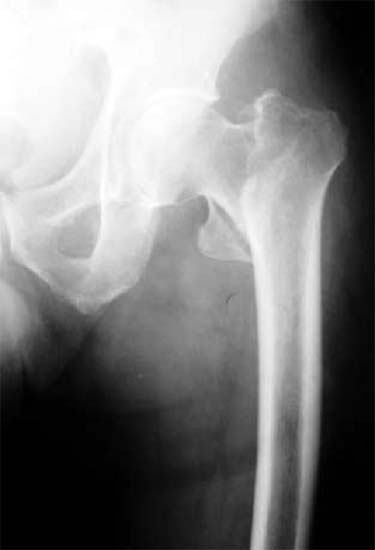

股骨粗隆间骨折,采用闭合股骨重建钉内固定。